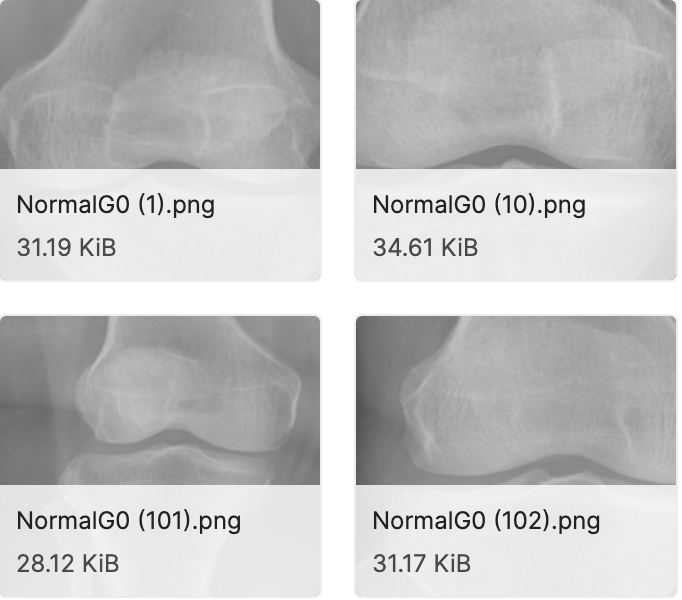

膝关节 X 射线图像数据集

数据集下载地址:http://m6z.cn/6aOU5G

该数据集包括从知名医院和诊断中心收集的 1650 张膝关节电子 X 射线图像。X 射线图像是使用 PROTEC PRS 500E X 射线机获取的。原始图像是 8 位灰度图像。每个 X 射线膝关节 X 射线图像均由 2 位医学专家根据 Kellgren 和 Lawrence 等级手动注释/标记。